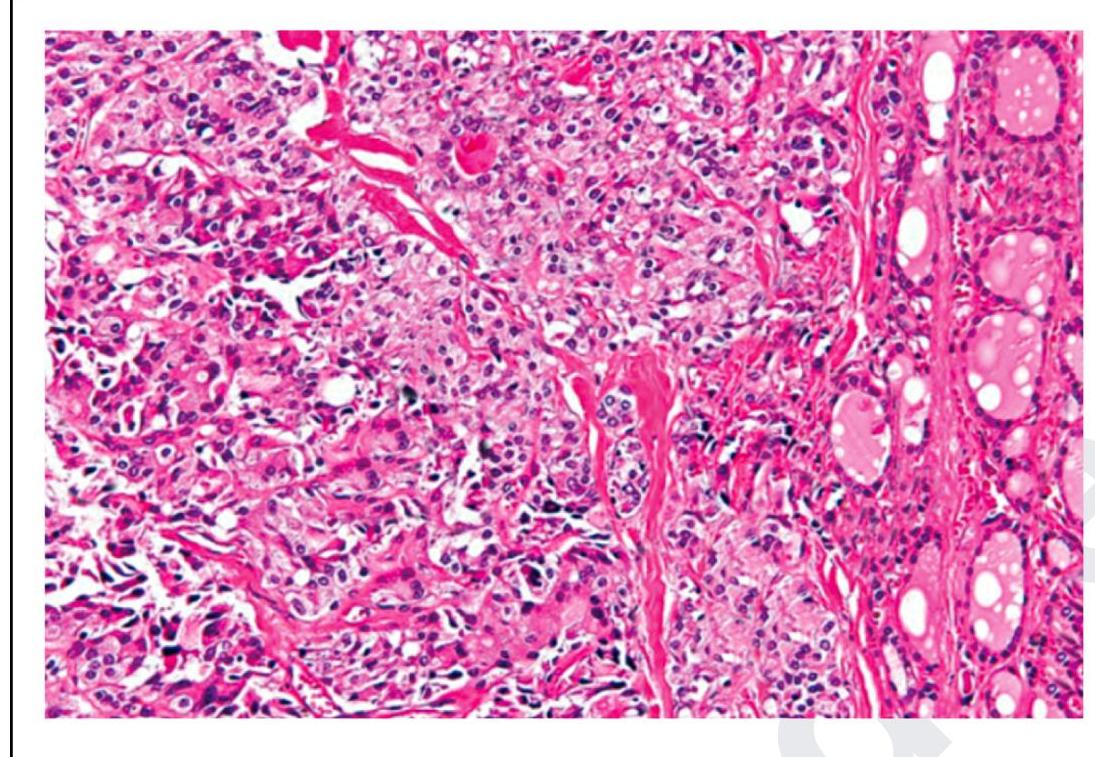

The following is a histopathological image of thyroid pathology. What is the diagnosis?

Explanation: ***Medullary carcinoma of thyroid*** - This image shows sheets and nests of **polygonal to spindle-shaped cells**, which are characteristic of medullary thyroid carcinoma, especially when mixed with an **amyloid stroma** (seen as amorphous eosinophilic material) [2]. - The presence of **neuroendocrine features** and the production of **calcitonin** are hallmarks of these C-cell tumors [1], [2]. *Papillary carcinoma of thyroid* - Characterized by **papillary architecture**, **ground-glass (Orphan Annie eye) nuclei**, nuclear grooves, and intranuclear cytoplasmic inclusions. - These features are not prominently seen in the provided image. *Follicular carcinoma of thyroid* - Defined by an invasive growth pattern of **well-differentiated follicular cells** forming follicles, with either capsular or vascular invasion [2]. - The image does not show classic follicular architectural patterns or clear evidence of invasion in the absence of a capsule. *Anaplastic carcinoma of thyroid* - This is a highly aggressive and undifferentiated tumor with **marked pleomorphism**, bizarre giant cells, and high mitotic activity [2]. - While there is some pleomorphism, the overall pattern and cellular morphology in the image are more consistent with medullary carcinoma than the extreme anaplasia. **References:** [1] Kumar V, Abbas AK, et al.. Robbins and Cotran Pathologic Basis of Disease. 9th ed. The Endocrine System, pp. 1102-1103. [2] Cross SS. Underwood's Pathology: A Clinical Approach. 6th ed. Common Clinical Problems From Liver And Biliary System Disease, pp. 428-431.